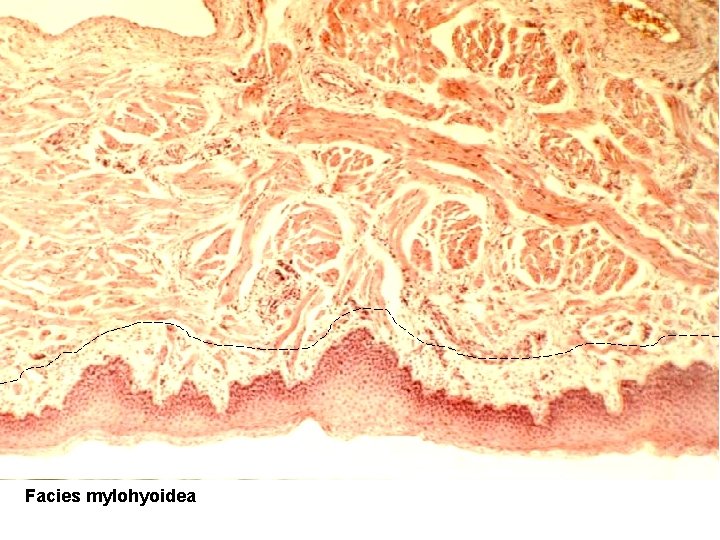

• Dorsum linguae: – tunica mucosa – papillae filiformes, fungiformes, vallatae, foliatae • lamina epithelialis – vrstevnatý dlažd. ep. , • lamina propria – řídké kolag. vazivo (tvoří papily) + kapiláry – aponeurosis linguae; (tela submucosa chybí! ) • Facies inferior (mylohyoidea): – tunica mucosa – hladký povrch (bez papil) • lamina epithelialis – vrstevnatý dlažd. ep. , • lamina propria – řídké kolag. vazivo, – tela submucosa – řídké kolag. vazivo. Podklad jazyka – příčně pruh. kosterní sval, kolagenní vazivo a slinné žlázky Pohyblivý svalový orgán – žvýkání a artikulace

apex linguae dorsum linguae - papillae svalová tkáň kosterní Gl. lingualis anterior (místo výskytu – na snímku chybí) facies mylohyoidea

Facies mylohyoidea